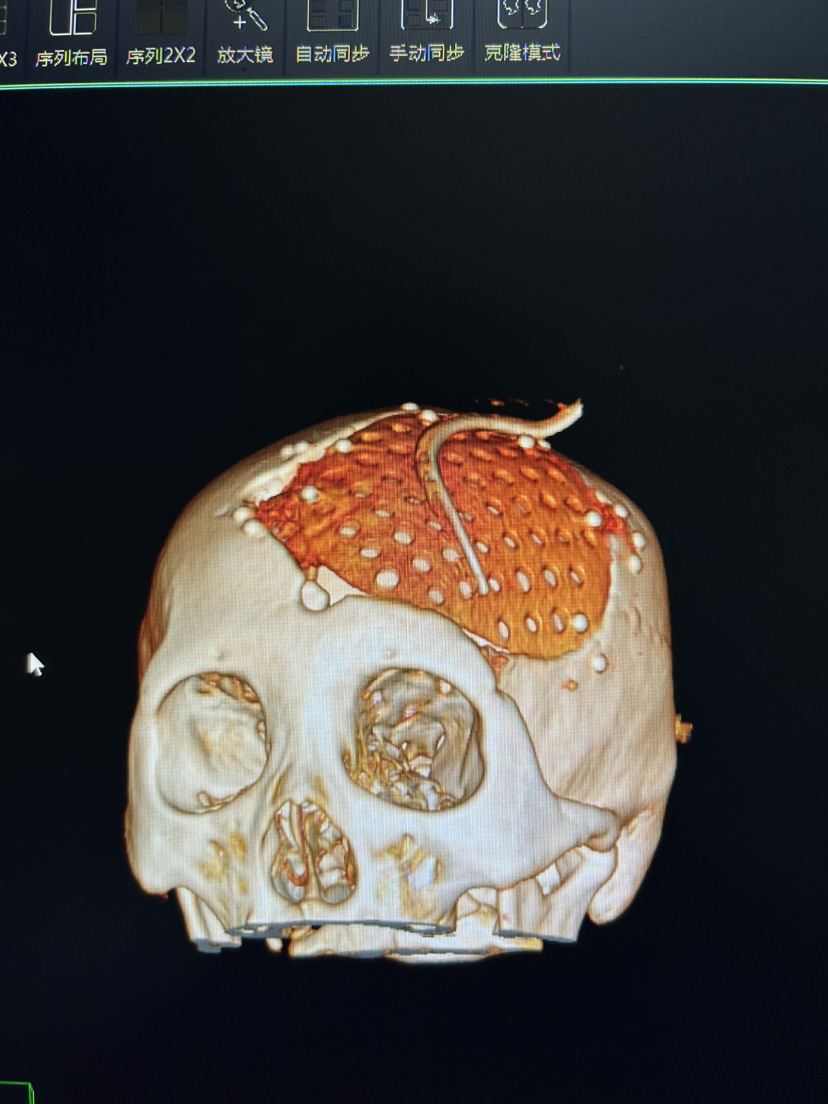

除了PEEK 钛网 本次用了超高分子量聚乙烯 颅骨修补

脑血管-烟雾病